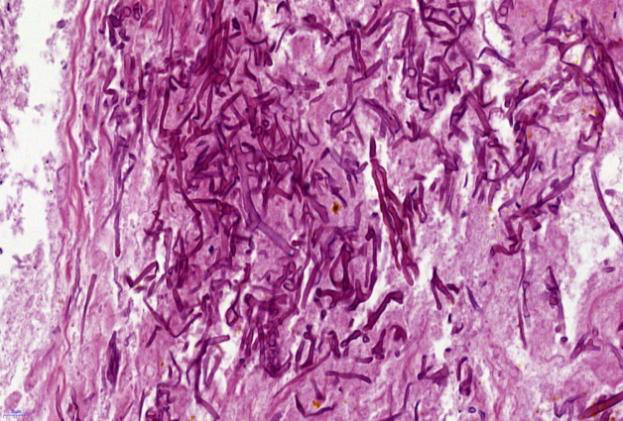

入院后应用导航支气管镜和超声内镜等精准定位技术,于右上叶前段、右下叶内基底段取出脓栓,并行病理活检:病理可见坏死组织内大量毛霉菌菌丝,并可见菌丝侵袭血管(图2)。支气管肺泡灌洗液及脓栓二代基因测序(mNGS)显示为微小根毛霉。最终确定诊断为急性髓系白血病合并肺毛霉菌病。

图2病理显示坏死组织内大量毛霉菌菌丝,并可见菌丝侵袭血管(GMS染色及弹力纤维染色)